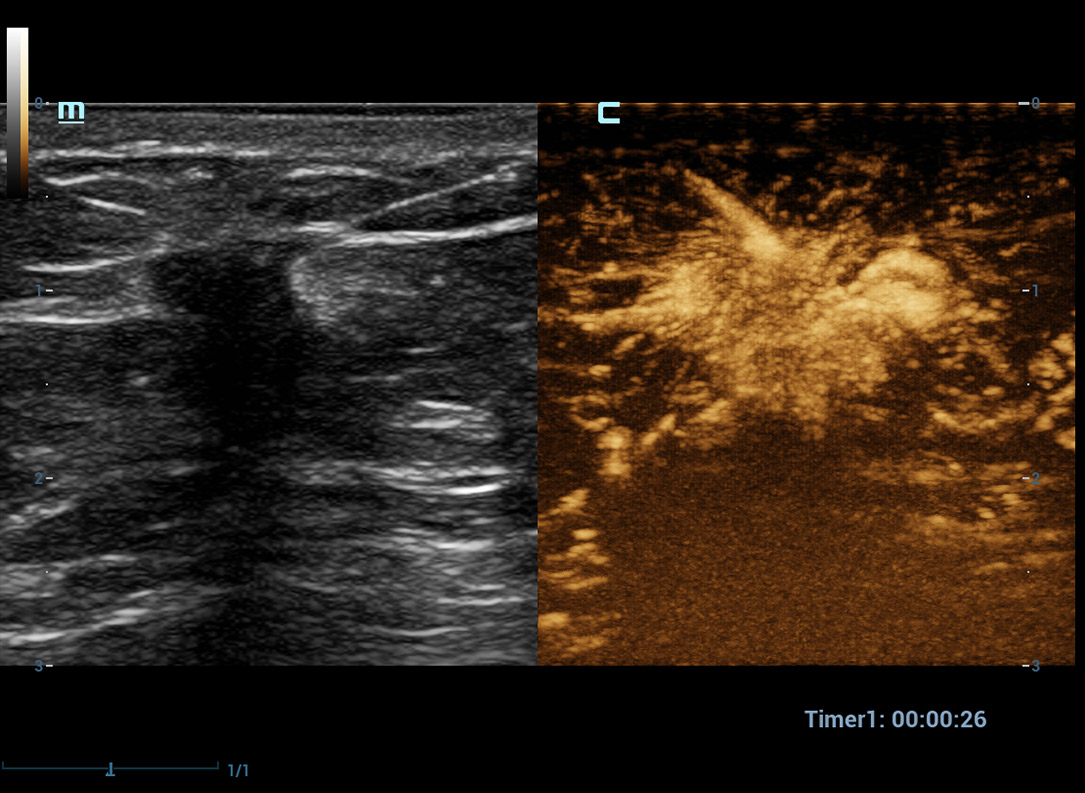

CEUS avan?ado

UWN+ (Ultra-Wideband Non-Linear) CEUS

CEUS ã Tumor maligno de mama

Ao utilizar tanto a segunda harm?nica quanto os sinais fundamentais n?o lineares, o UWN+ permite alta sensibilidade dos sinais das bolhas e maior dura??o de perfus?o com baixo MI, auxiliando nas avalia??es de tumores.

CEUS ã Massa mamûÀria